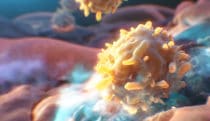

Killer T cells targeting tumor cells